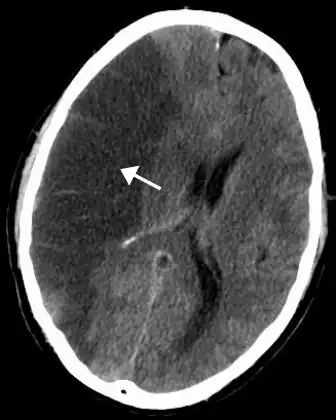

![]() | |

| CT scan of the brain showing a prior right-sided ischemic stroke from blockage of an artery. Changes on a CT may not be visible early on.[1] | |

The biggest risk factor for stroke is high blood pressure.[7] Other risk factors include high blood cholesterol, tobacco smoking, obesity, diabetes mellitus, a previous TIA, end-stage kidney disease, and atrial fibrillation.[2][7][8] An ischemic stroke is typically caused by blockage of a blood vessel, though there are also less common causes.[13][14][15] A hemorrhagic stroke is caused by either bleeding directly into the brain or into the space between the brain's membranes.[13][16] Bleeding may occur due to a ruptured brain aneurysm.[13] Diagnosis is typically based on a physical exam and supported by medical imaging such as a CT scan or MRI scan.[9] A CT scan can rule out bleeding, but may not necessarily rule out ischemia, which early on typically does not show up on a CT scan.[10] Other tests such as an electrocardiogram (ECG) and blood tests are done to determine risk factors and rule out other possible causes.[9] Low blood sugar may cause similar symptoms.[9]